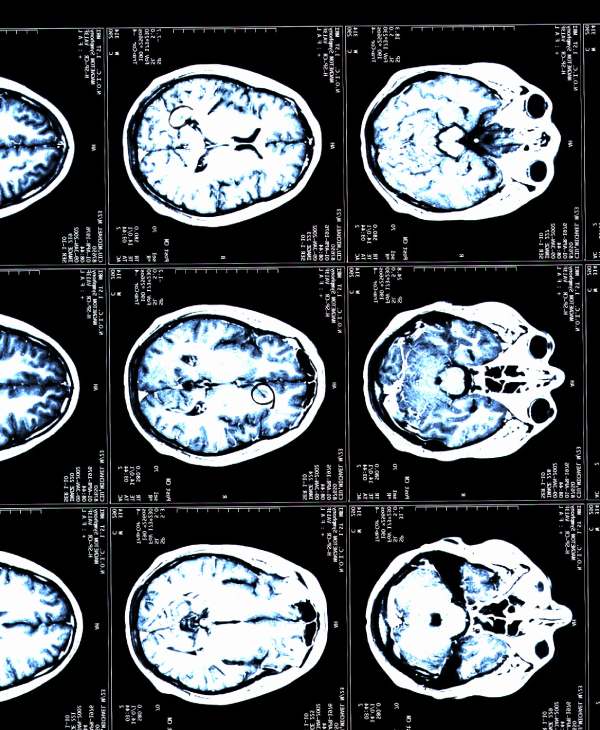

Imagen de una resonancia magnética